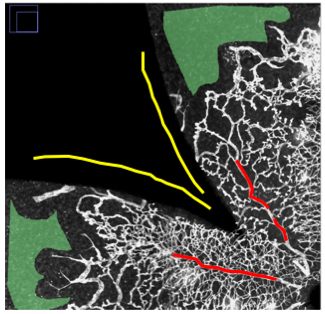

Figure 3. Training the Weka Segmentation Tool. The Trainable Weka Segmentation Tool in FIJI allows users to apply various machine-learning

segmentation algorithms to an image. We created a library of four sub-images with manually selected portions of the avascular

retina (green), the vascular retina (red), and background (yellow). We then used these to train the Weka classifier.